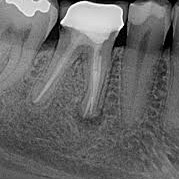

La endodoncia posterior es un tratamiento odontológico que se realiza en los dientes posteriores...